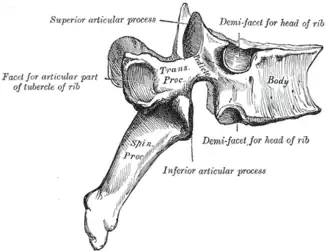

| A diagram of a human vertebral body. With Baastrup's sign, the posterior spinous process, pointing down and to the left, is abnormally thickened due to repetitive microtrauma. | |